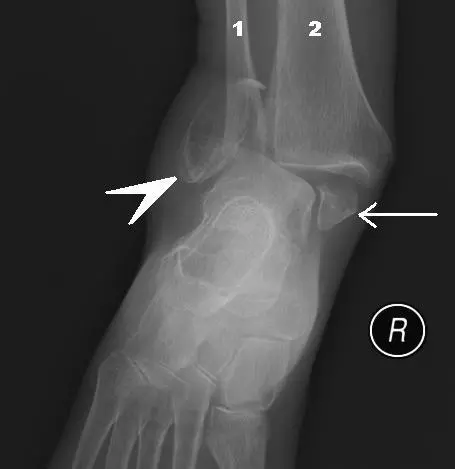

Diagram - X-ray of fracture of the lateral and medial malleoli. A fracture of both the lateral and medial malleoluses is known as a bimalleolar fracture

Creative commons source by Steven Fruitsmaak [CC BY-SA 4.0 (https://creativecommons.org/licenses/by-sa/4.0)]

Bimalleolar (medial and lateral malleoli) and trimalleolar (medial and lateral malleoli and posterior aspect of the tibia) fractures are commonly described by the malleoli involved. The historical term Pott's fracture is variably defined and is used less often in modern practice. Pott’s fractures are far more common than fracturing a single malleolus because of the ligaments that secure the mortise of the ankle joint. A force applied in one direction often cause ligamentous damage on the other side of the ankle due to talar shift, which can cause a fracture at the attachments of the ligaments.